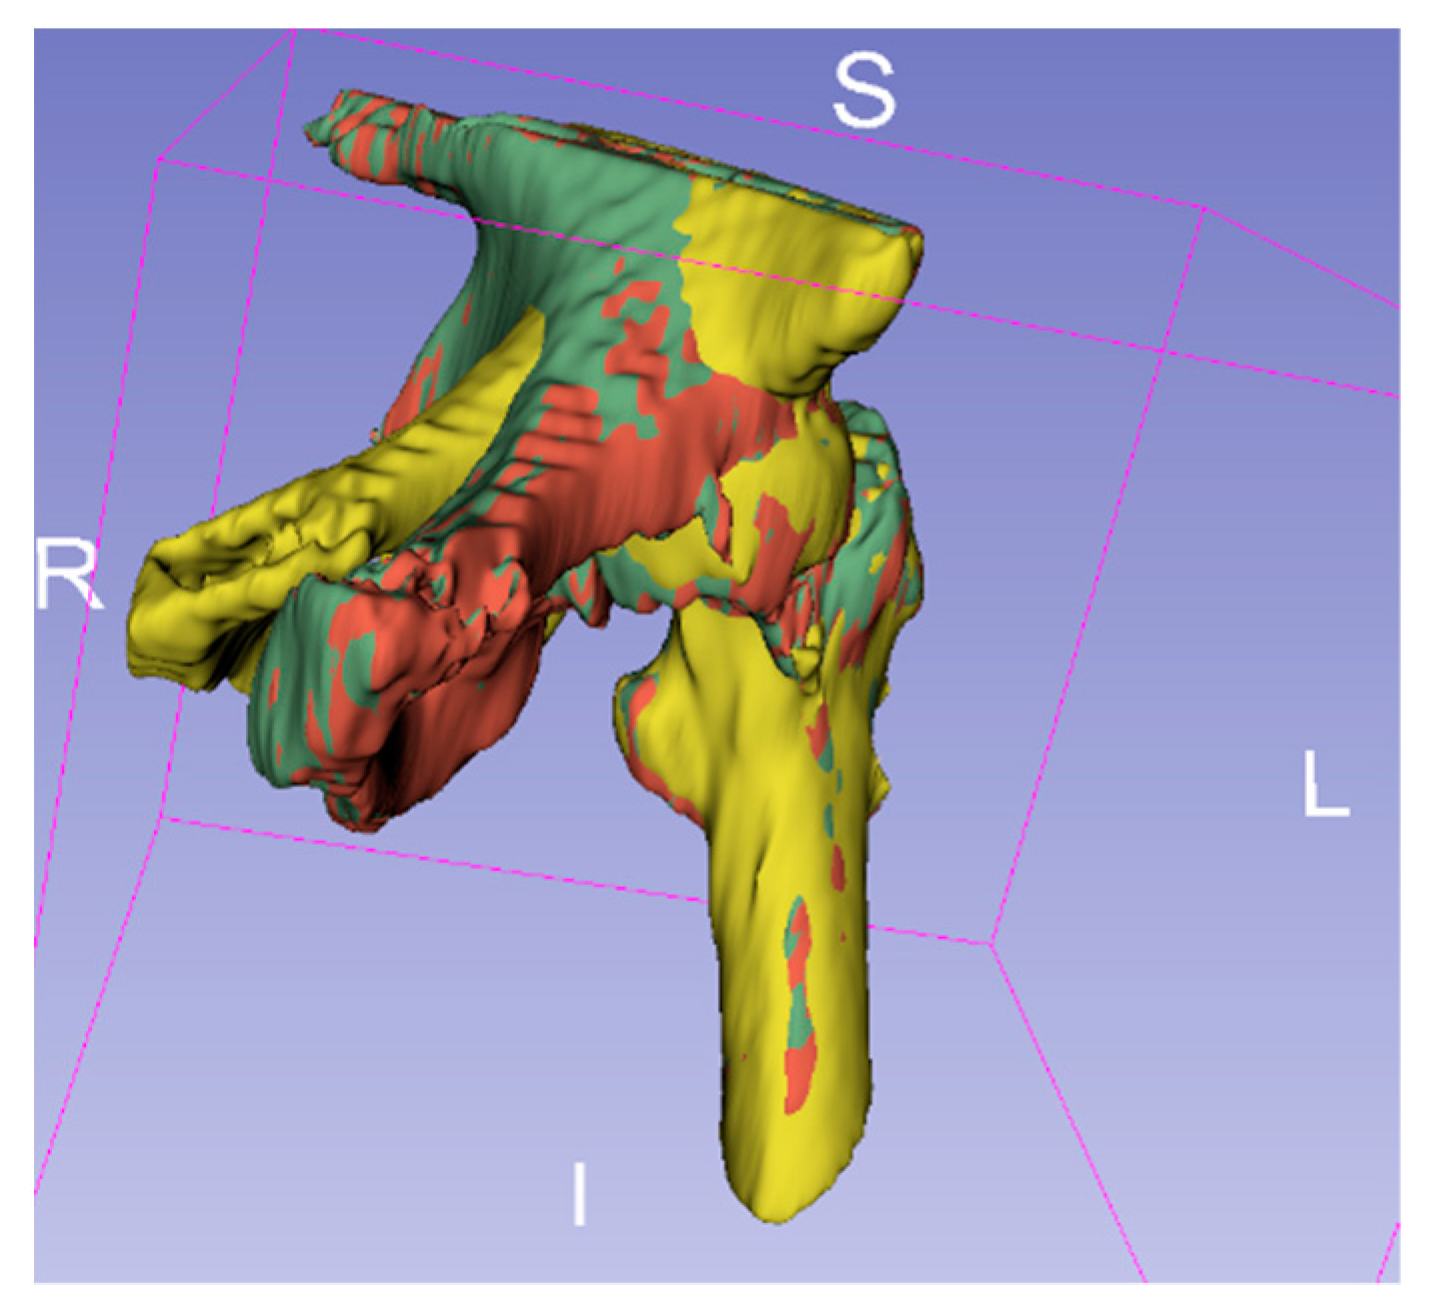

The fixed image and floating image after fine registration are shown in Figure 10. In the two CT images after alignment, the proximal femur parts without the femoral head are overlapped and served as the reference. Observed in 3D space, the proximal pin and distal pin are in the same spatial coordinate system, and after 3D reconstruction, the voxel data of pins in CT are transformed into point cloud data, as shown in Figure 11.

Figure 10.

CT images after registration: (a) fixed images; (b) fine-aligned floating images; (c) the two images in the coordinate system with the overlapping femur as the reference.

Figure 11.

3D point clouds of proximal pins and distal pins in the same spatial coordinate system for both previous and posterior CT images. The purple point cloud is part of the proximal femur and pelvis. The green and blue point clouds represent the proximal and distal pins obtained from the first postoperative CT scan. Gold and red point clouds represent the proximal and distal pins from the second CT image after the previous CT scan, respectively.